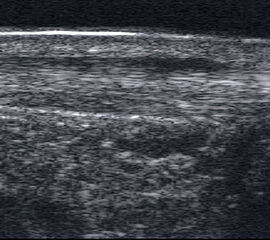

Lymphödem am oberen Sprunggelenk

Echogene Verdickung im Subkutangewebe bei Lymphödem

Abbildung 8

Lagerung: Rückenlage.

Schnittebene: Ventraler LS über dem OSG.

Referenzstrukturen: Distale Tibia und Talusrolle, darüber Gelenkkapsel. Befunde: Echogene Verdickung subkutan (Abb. 8), hier peronäal oberhalb des OSG. Bei Varicosis sind in der Subkutis erweiterte Venenkomplexe mit echoarmem Lumen und positivem Doppler-Signal zu sehen.